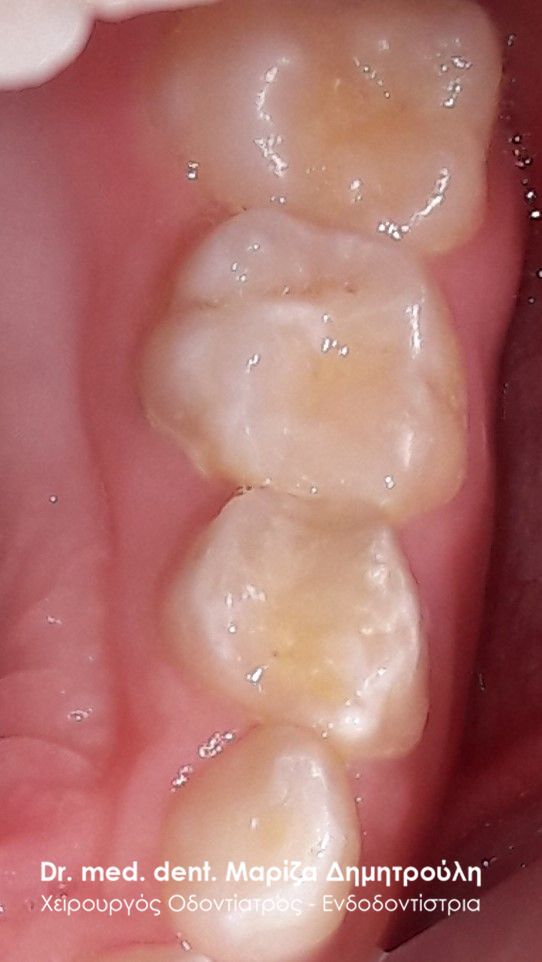

ΠΡΙΝ

ΜΕΤΑ – Σφράγισμα νεογιλού δοντιού και sealant μόνιμου δοντιού